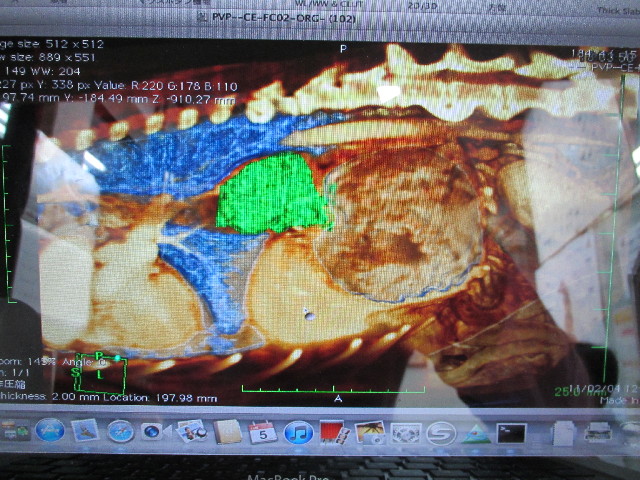

これは、食道に腫瘍があることがわかった2011年2月4日に日本大学動物病院でMRI検査をしたものに着色した画像。

緑色の部分がべべちゃんの食道の腫瘍です。